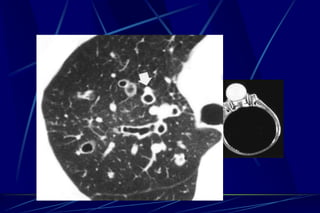

Bronchiectasis

Bronchiectasis is defined as localized bronchial

dilatation. (signet-ring sign)

bronchial wall thickening

lack of normal tapering with visibility of airways in

the peripheral lung

mucus retention in the broncial lumen

associated atelectasis and sometimes air trapping

Signet-Ring Sign

A signet-ring sign represents an axial cut of a dilated bronchus

(ring) with its accompanying small artery (signet).

Tram Tracks

Bronchial dilation with lack of tapering .